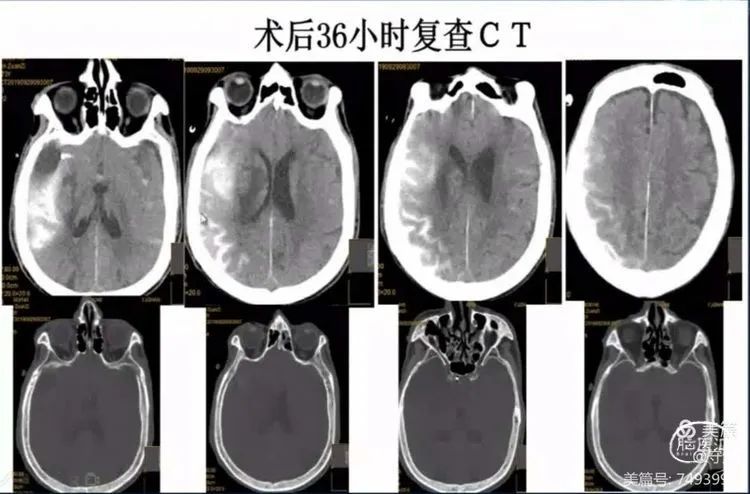

CT显示:少量出血可能。

20分钟后复查CT出血未明显增加。